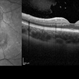

- Fundus camera

- Fundus photograph of a 72-year-old man with a retinal astrocytoma of the left eye.